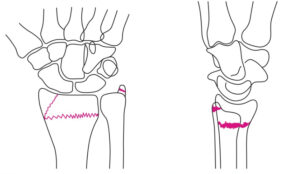

| 検査 | 【身体所見】 手関節腫張、フォーク状変形 【画像検査】 Xp:手関節2方向で撮像し骨折線を探す、尺骨茎状突起骨折の併発も確認する。 小児の場合はSalter-Harris分類を行う![]() |

| 病態 | 転倒時の肘伸展位において手をついた(FOOSH)時に生じる骨折で、手根骨骨折の約70%を占める(その他の手根骨骨折は三角骨骨折、月状骨骨折が多い)。舟状骨は血行性に乏しく、骨折により容易に阻血となり、骨壊死や偽関節といった合併症を引き起こすため、舟状骨骨折を見逃すと問題となる(occult骨折多い)。![]() |

| 検査 | 【画像検査】 Xp:手関節2方向で撮像し骨折線を探し、関節内骨折の場合は手術、関節外骨折の場合は保存加療となる。 ![]() |